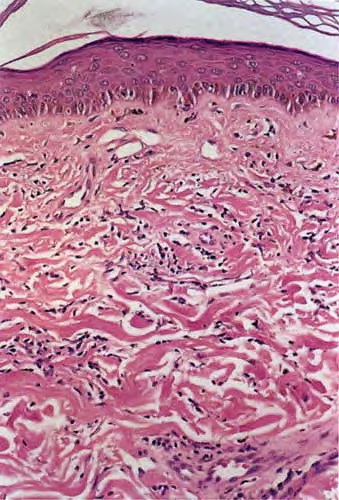

morphea